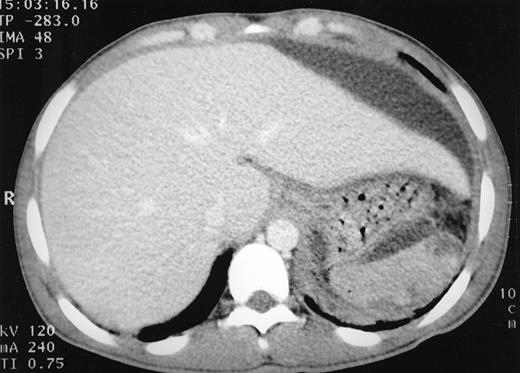

CT scan of abdomen showing a large subcapsular collection of fluid compressing the left lobe of the liver. Liver and spleen appear normal.

A 21-year-old man with homozygous sickle cell disease presented with a 3-week history of epigastric pain, anorexia, and weight loss of 5 kg. On examination he was in considerable discomfort and was febrile (temperature 38.5°C) and tachycardic (110 beats per minute [bpm]). Lung fields were clear, oxygen saturation was 100% on air. The liver was enlarged to 6 cm below the costal margin with tenderness over the left lobe. Blood count revealed a hemoglobin level of 7.3 g/dL (2 g/dL below his steady-state value) and marked neutrophilia (46.0 × 109/L) with left-shift. Liver function tests showed moderate elevation in gamma-glutamyl transferase (200 IU/L; normal range, 5 to 55 IU/L) but were otherwise unremarkable. Differential diagnosis for such a presentation in sickle cell disease includes hepatic sequestration, cholecystitis, and mesenteric sickling crisis. The patient was treated with analgesics, intravenous broad spectrum antibiotics, and exchange blood transfusion. Ultrasound and computed tomography (CT) abdomen showed a subcapsular fluid collection 10 cm in diameter related to the left lobe of the liver, with no evident intrahepatic, biliary, or splenic pathology (Fig 1). On percutaneous aspiration 250 mL pus was obtained. Microscopy showed yeasts and polymorphonuclear leukocytes, and Candida albicans was isolated from pus and blood cultures. He was treated with intravenous fluconazole and percutaneous drainage of abscess using an indwelling pigtail catheter. A total of 1.5 L of pus was drained over a 4-week period until no fluid remained. He has since remained well, with no recurrence of the abscess.